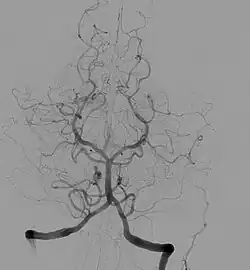

O polígono de Willis ou círculo de Willis (também chamado de círculo arterial cerebral ou círculo arterial de Willis) é um círculo de artérias que suprem o cérebro. Foi nomeado em homenagem a Thomas Willis (1621-1673), médico inglês.[1]

- Artéria cerebral anterior (esquerda e direita)

- Artéria comunicante anterior

- Artéria carótida interna (esquerda e direita)

- Artéria cerebral posterior (esquerda e direita)

- Artéria comunicante posterior (esquerda e direita)

A artéria basilar e a artéria cerebral média, apesar de irrigarem o cérebro, não são consideradas parte do polígono.[2]

As carótidas internas direita e esquerda originam-se das artérias carótidas direita e esquerda. As artérias cerebrais anteriores e médias e as artérias comunicantes posteriores originam-se na trifurcação da artéria carótida interna. As artérias cerebrais posteriores direita e esquerda originam-se da artéria basilar, que é formada pelas artérias vertebrais direita e esquerda. As artérias vertebrais, por sua vez, origina-se nas artérias subclávias. A artéria comunicante anterior conecta as duas artérias cerebrais anteriores.